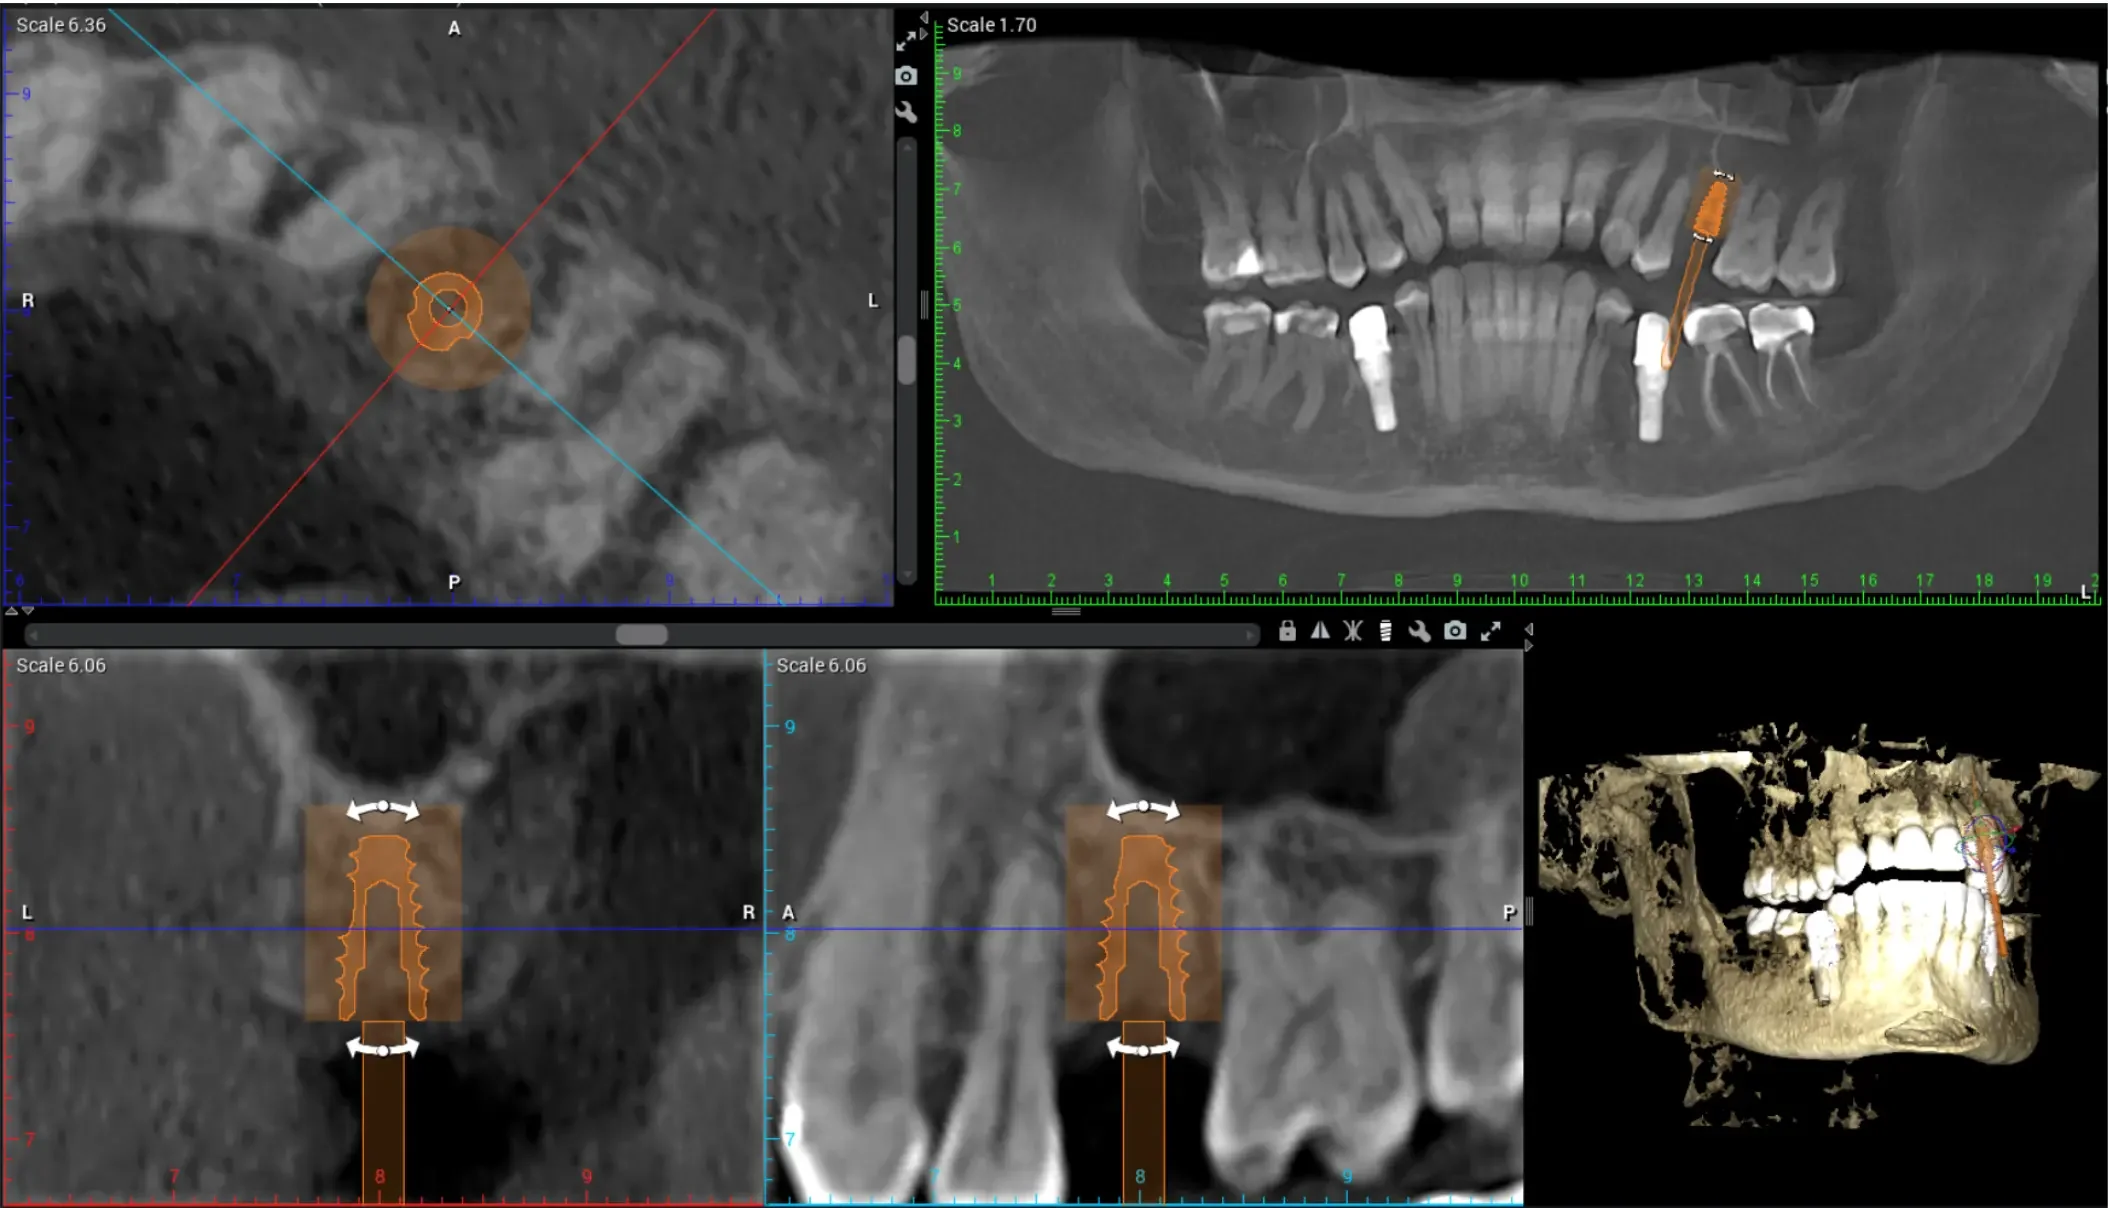

3D Imaging & Guided Placement for more predictable results 🔍

3D Cone Beam CT Imaging (CBCT)

Digital Implant Planning Software

Option for Guided Implant Surgery